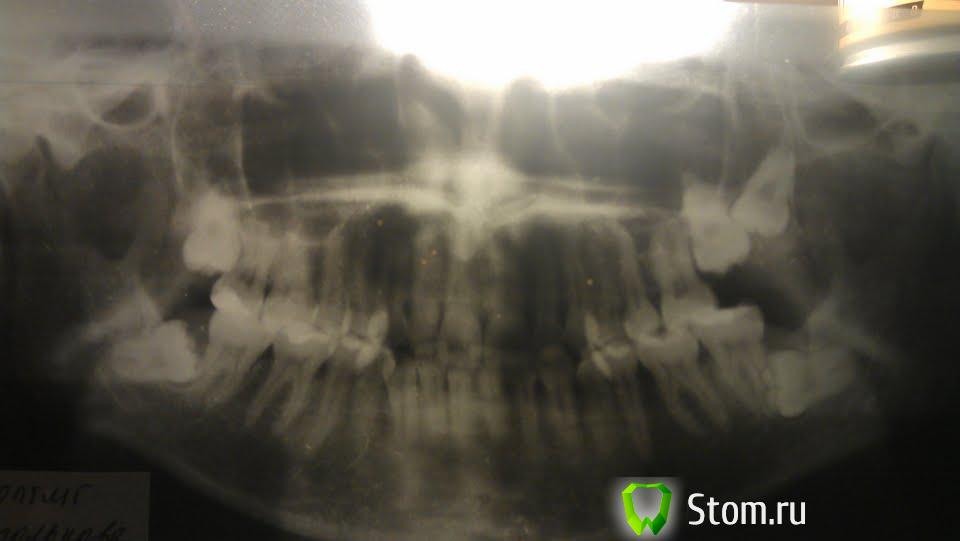

sus Опубликовано 20 марта, 2012 Поделиться Опубликовано 20 марта, 2012 (изменено) Здравствуйте, уважаемые доктора! Буду очень благодарна, если выскажете ваши мнения по моему случаю.Жен, 27. Ситуация многолетняя, стабильная в плане положения зубов. В последние годы появилась и прогрессирует рецессия десен (более темные - более ранние, лет 6, крайнее оголение "новой" шейки - месяца 4 назад). Поскольку я понимаю, что зубы расположены не наилучшим образом, плюс рецессия, хочу ситуацию поправить. При этом слышу абсолютно разные рекомендации по выбору системы и длительности ношения. Я бы ОЧЕНЬ хотела Инвизалайн. "Подпиливание" в межзубных промежутках, как я понимаю, мне в любом случае нужно делать: места взять неоткуда, угол резцов для "выворачивания наружу" коронок изменять нельзя, т.к.он нормальный. Зубы 18 и 48, которые есть на снимке, уже удалены. По поводу 28 и 27 я уже создавала тему (http://forum.stom.ru...z-zubov-udalit/), повторю здесь свой вопрос: который их них лучше удалять? Если нужно, я могла бы выложить набор фото покрупнее (от другого ортодонта, фото с бумажной фотографии), этот файл таким прислали. Большое спасибо! Изменено 20 марта, 2012 пользователем sus Ссылка на комментарий